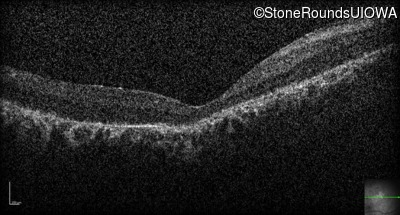

Optical Coherence Tomography - Right - 20/200 +1

Exemplar / OCT Stack